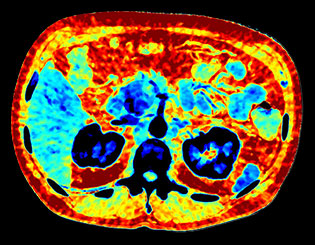

Obraz efektywnej liczby atomowej

Tworzy w oparciu o liczbę atomową tkanki widocznej na obrazie kodowaną kolorem mapę, której można użyć do scharakteryzowania różnych tkanek, np. kamicy nerkowej.